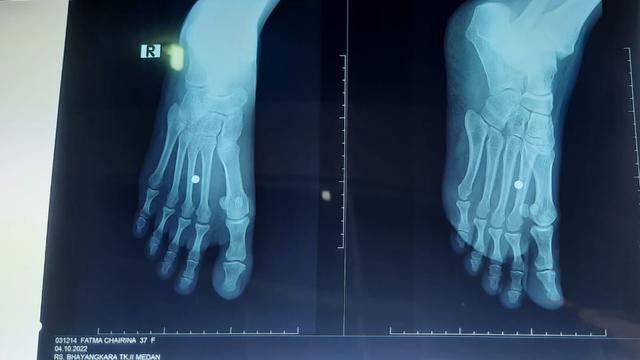

Korban kemudian dibawa ke Rumah Sakit (RS) Brimob Polda Sumut, Jalan KH Wahid Hasyim, Medan, untuk mendapatkan perawatan. Korban harus dioperasi kecil untuk mengeluarkan peluru yang masih ada di kakinya.

"Operasi untuk mengeluarkan proyektil yang masih bersarang di kaki korban," ungkapnya.

Diungkapkan Fathir, korban pada saat kejadian terkena tembakan airsoft gun. Diduga pelaku yang masih berstatus OTK menembak korban menggunakan airsoft gun, dan mengenai bagian kaki korban.

"Dia (korban) luka terkena airsoft gun," tandasnya.